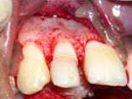

Labial Soft Tissue

Reflected

Tooth with Fracture Extending Sub-Gingivally

Palatal Soft Tissue